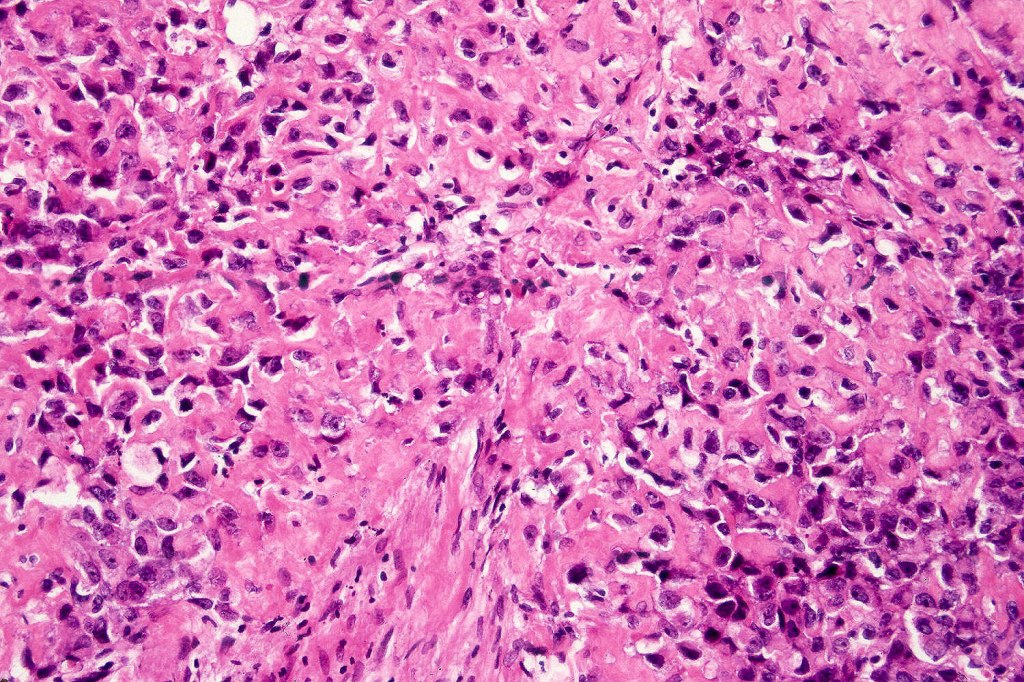

•Smooth muscle fibroblastic/myofibroblastic

•Rhabdomyosarcomatous